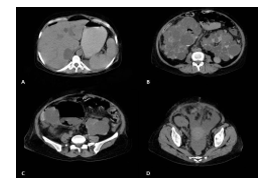

Abdominal computed tomography (CT) scan showed pneumoperitoneum and free fluid in the pelvis and abdomen, plus a 98 mm dominant inflated cyst in the lower pole of the right kidney. Moreover, multiple liver cysts and collapse of the distal segment of the ileum were noted (Figure 1).

Figure 1- CT scans of the patient. A: free air in the peritoneal cavity; B: bilateral polycystic kidney; C: ruptured infected cyst of the right kidney; D: free fluid in the pelvic cavity